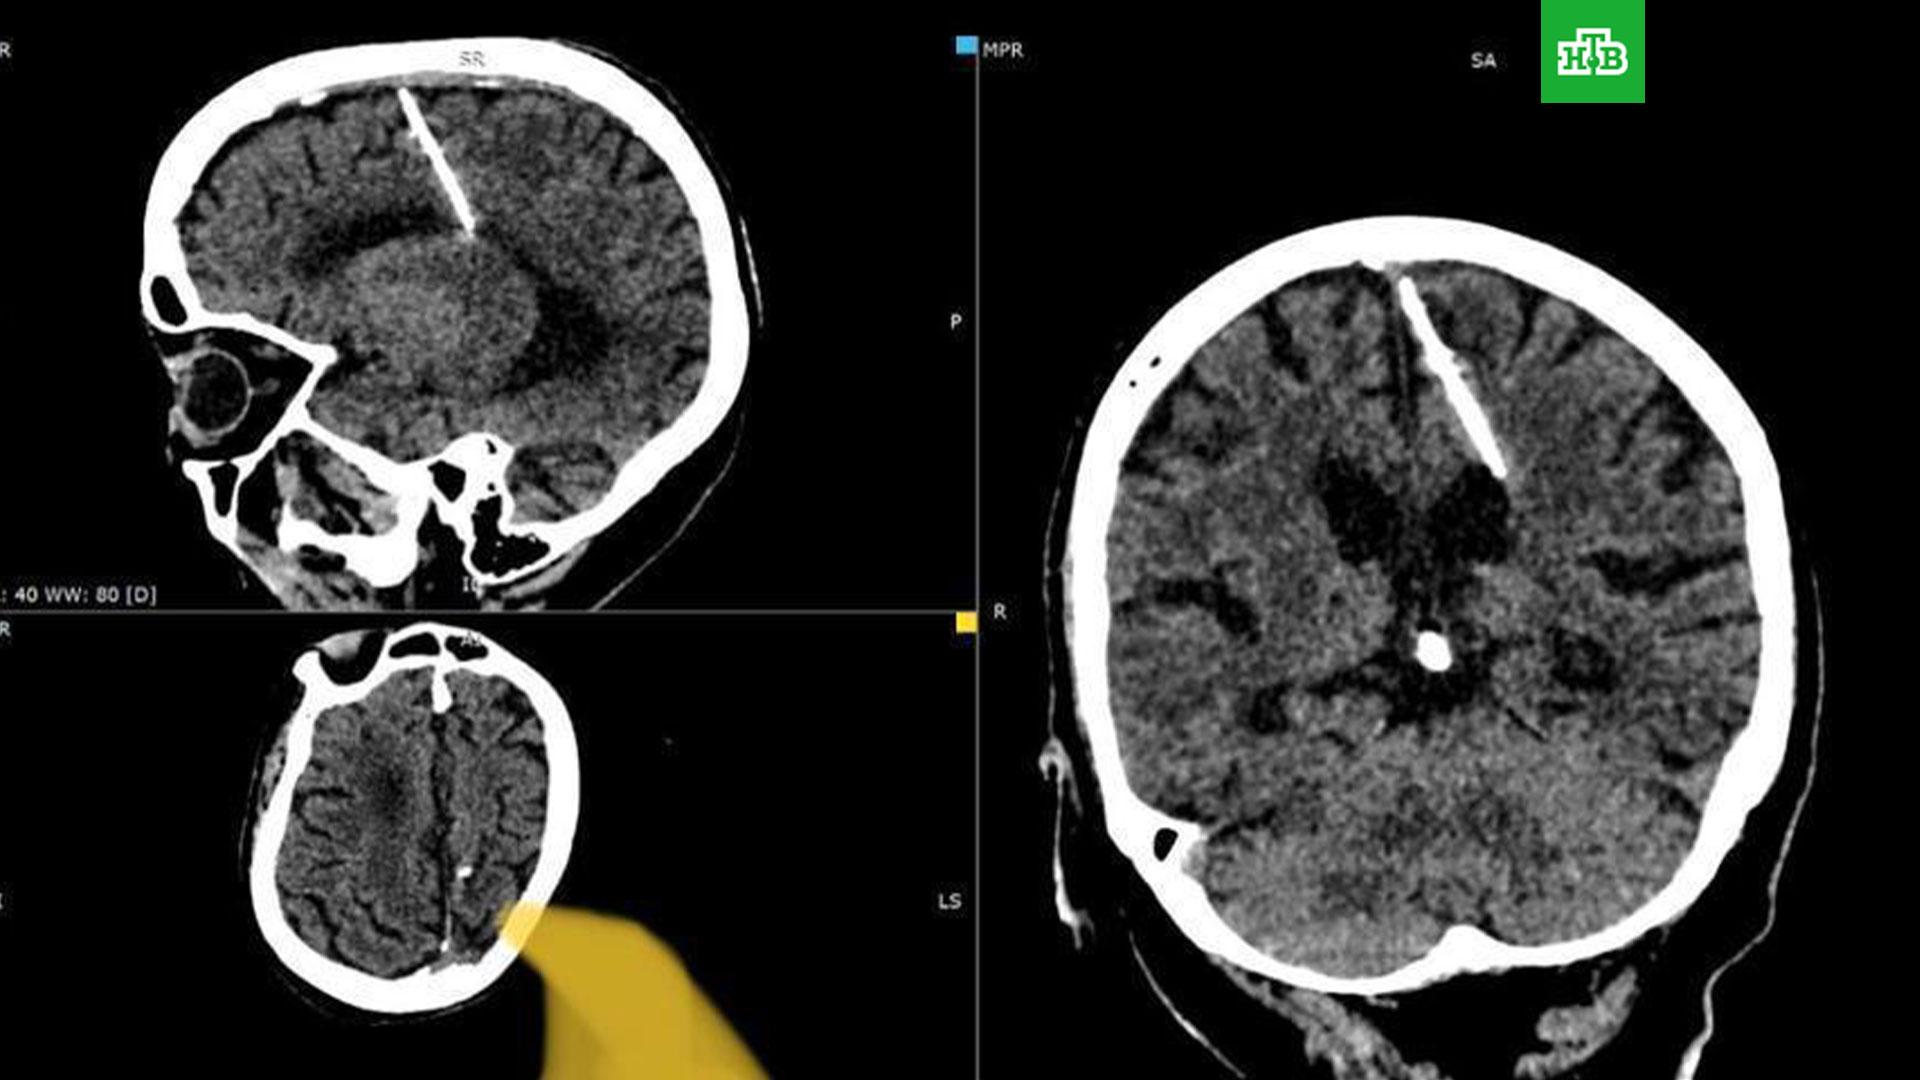

Сахалинские медики нашли в голове у пенсионерки трехсантиметровую иглу.

Врачи решили не доставать инородное тело, так как это могло только ухудшить состояние пациентки. На головные боли женщина никогда не жаловалась.

Как рассказали в сахалинском минздраве, женщина жила с иглой в голове с рождения. Иглу в мозг воткнули родители, которые пытались таким образом убить дочь в сложное военное время. В ведомстве отметили, что такие случаи тогда были не редкостью — младенцу в родничок вставлялась тонкая игла, которая повреждала мозг. Позднее родничок затягивался, скрывая следы преступления, малыш же погибал.